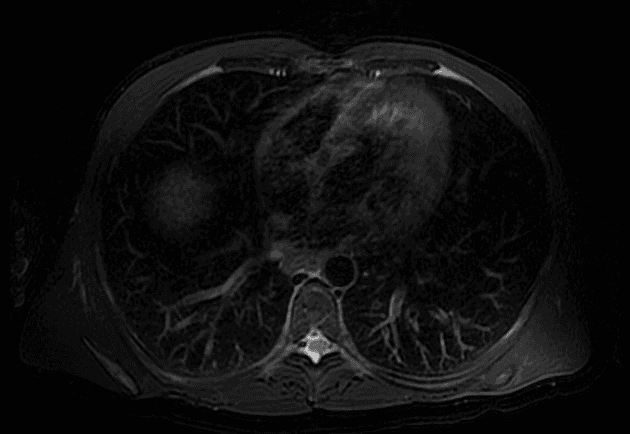

Axial DWI

Bệnh nhân có tiền sử bệnh gan mạn tính và đã cắt túi mật (cholecystectomized), đến khám do các đợt ứ mật, được bác sĩ chuyên khoa gan chuyển đến dịch vụ chẩn đoán hình ảnh.

- Gan biến dạng (xơ gan - cirrhosis).

- Co kéo màng gan (capsular retractions) trùng khớp với các tổn thương có bờ lõm, hiện diện dưới dạng các vùng hình tam giác, đáy ngoại vi và đỉnh ở rốn gan (hilar vertex), nằm ở phân đoạn VI, VIII, IV và mức độ nhẹ hơn ở phân đoạn I.

- Các tổn thương này giảm tín hiệu trên hình ảnh T1 (hypointense), tăng tín hiệu trên T2 (hyperintense), hình ảnh khuếch tán (DWI), và tăng quang (enhancement) tiến triển theo thời gian sau khi tiêm thuốc cản quang tĩnh mạch.

- Ở các khu vực này, ống mật trong gan (intrahepatic bile duct) giãn (ectasic).

- Các hình ảnh này phù hợp với (consistent with) xơ gan lan tỏa (confluent hepatic fibrosis).